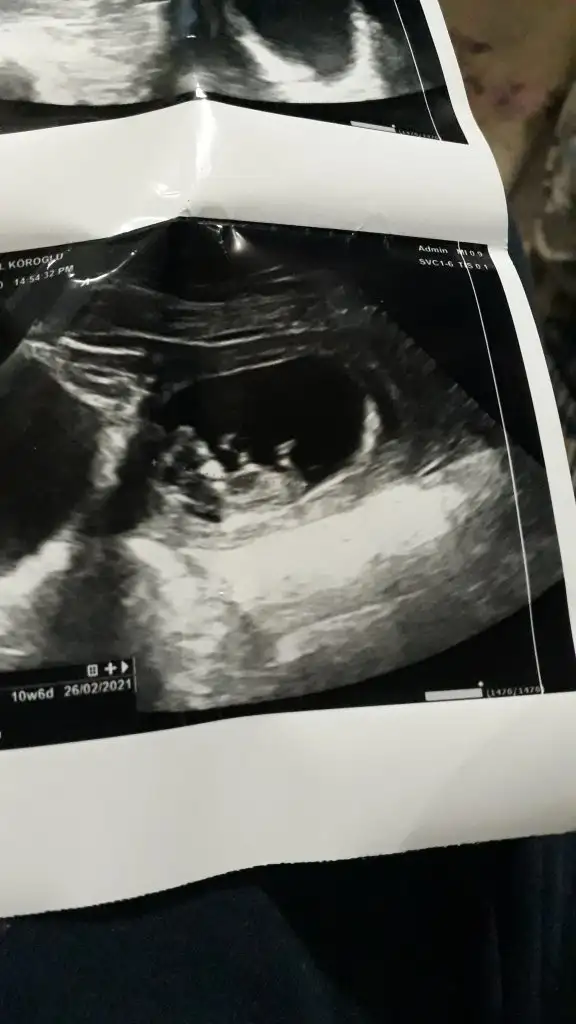

Merhaba ben dün hastaneye gitmiştim 15.hafta görüntüsünü de atıyorum bi bakabilir mirun bi tahmini oldu da siz de bi bakın

Ben 11 12 13. Hafta buna bakıyorum eğer gördüğüm boşluk ise sanki kız gibi geldi istediğim haftalar varsa paylaşınMerhaba ben dün hastaneye gitmiştim 15.hafta görüntüsünü de atıyorum bi bakabilir misiniz doktorun bi tahmini oldu da siz de bi bakın istiyorum ikrameyra canım sen de bi bakabilir misin rica etsem

O haftalar yok canım dr 12.haftada kıza benzettim ama bu haftalarda çok değişir demişti. 15+3 te gittiğimizde de erkek dedi. Ama emin olamadım once öyle deyip şimdi böyle deyince ben de şaşırdım. Sence değişir mi bu haftadan sonra ?Ben 11 12 13. Hafta buna bakıyorum eğer gördüğüm boşluk ise sanki kız gibi geldi istediğim haftalar varsa paylaşın